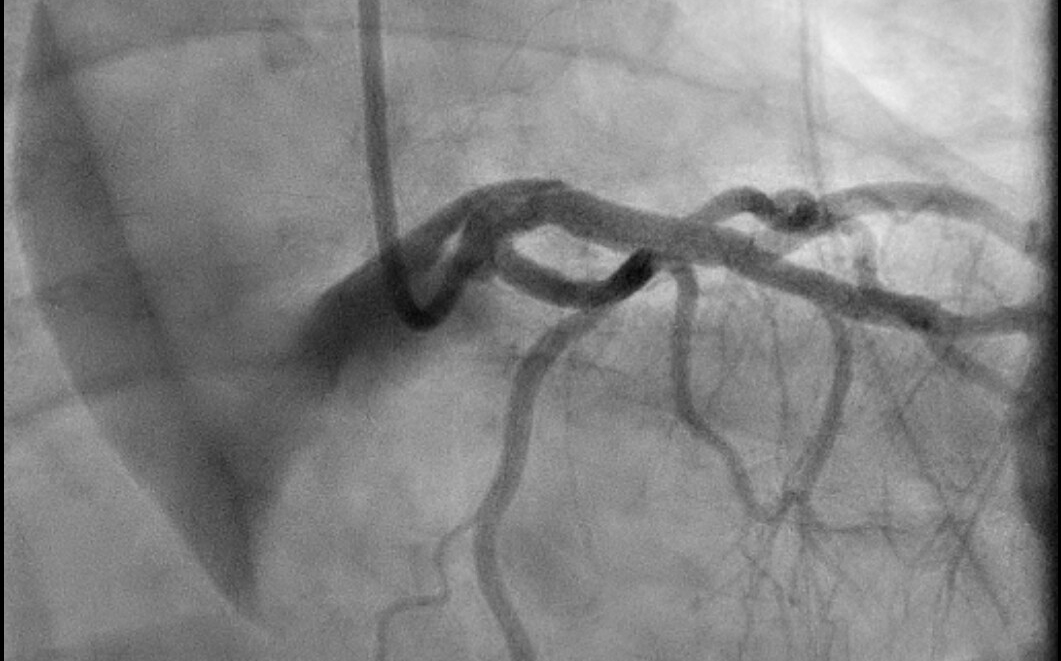

Clinical Case: A 66-year-old female with, history of paroxysmal atrial fibrillation on apixaban and DVT, presented to the emergency department due to epigastric discomfort. Ischemic evaluation was negative. Two weeks later patient had a follow up visit and reported ongoing symptoms. Coronary CT angiography was completed and showed 70-75% stenoses of Left Main and Left Anterior Descending arteries. The patient underwent coronary angiogram, confirming the diagnosis. During guide catheter introduction for IFR measurement, the artery was dissected and the dissection flap extended retrograde to the aortic root and ascending aorta. Prompt placement of a drug eluting stent in the left main was performed. Post-dilation, the dissection flap had closed. Patient was started on IV cangrelor, high dose beta blocker and transferred to the cardiac ICU. CTA chest demonstrated dissection flap in ascending and descending aorta. Cardiothoracic surgery was consulted and opted to observe with follow up imaging as patient was hemodynamically stable. Follow up CT chest showed a stable dissection flap, IV cangrelor was switched to aspirin and clopidogrel, and home apixaban was resumed. Hospital course was uneventful except for an episode of atrial fibrillation with rapid ventricular response, treated accordingly with beta blocker and amiodarone. CT chest in one month demonstrated an increase in aortic intramural thickness from 3.3mm to 9mm. Aspirin and apixaban were discontinued and retrievable IVC filter was placed. CT chest one month later demonstrated complete resolution of ascending intra-mural hematoma. Patient’s apixaban was resumed. CT chest in two weeks showed no new hematoma. IVC filter was removed and patient remained asymptomatic during the follow up course. Given patient had family history of aortic aneurysm and dissection, genetic testing was pursued and was negative.